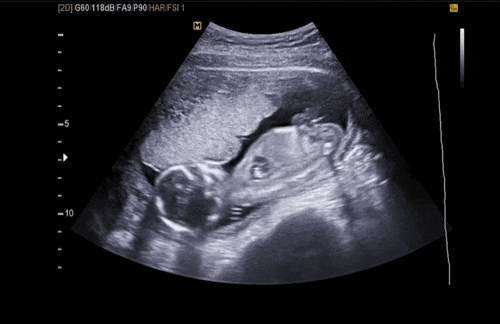

임신일기 14주차-16주차❤️

안녕하세요. 킴아입니다. 드디어 초기는 지나고 중기로 슬슬 넘어가는 임산부가 되었어요. 초기 때 이벤트...

[초음파앨범 추천]육오빠 초음파앨범 내돈내산 후기❤️

안녕하세요. 킴아입니다. 병원 진료 받으면서 모아둔 초음파사진,, 17주차 되면서 보니 어마어마한 양이 되...

임신일기 10주차-13주차(니프티검사)❤️

안녕하세요. 킴아입니다. 임신 10주차, 11주차, 12주차에는 산부인과 진료가 없어서 13주차 기록 남기기 임...